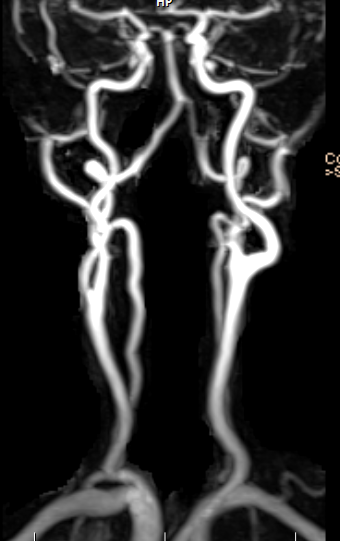

3. MRA (자기공명혈관조영술): 뇌혈관 건강을 위한 중요 검사

MRA(Magnetic Resonance Angiography)는 MRI의 한 종류이지만, 특별히 혈관을 더 자세히 보기 위한 검사입니다. 특히 뇌혈관의 상태를 확인하는 데 매우 유용합니다.

왜 중요할까요? 우리 뇌 속의 혈관에 기형(이상한 모양)이 있는지, 특히 뇌동맥류(뇌혈관이 풍선처럼 부풀어 오른 것)가 있는지를 확인하는 데 필수적입니다. 뇌동맥류는 평소에는 아무런 증상 없이 지내다가, 어느 날 갑자기 터지면 뇌출혈로 이어져 생명을 잃거나 심각한 장애를 남길 수 있는 무서운 질환입니다. 마치 언제 터질지 모르는 시한폭탄과 같다고 할 수 있어요.

- 첫 뇌 MRI 촬영 시 필수: 생애 처음으로 뇌 MRI를 찍을 일이 생겼다면 이때 반드시 MRA도 함께 찍어보는 것을 강력히 권장합니다. 뇌 속 혈관의 기형이나 터질 가능성이 있는 뇌동맥류가 있는지 미리 확인하는 것이 매우 중요합니다. 이런 이상 있는 혈관들은 평소에 아무 증세도 없이 조용이 있다가 갑자기 문제를 일으키니 평소에 확인해볼 기회가 있을 때에 미리 확인해두는 것이 좋습니다.

- 수년 후 재검사 시에도 고려: 만약 3~5년 전에 뇌 MRI를 찍었더라도, 이번에 다시 찍을 일이 생긴다면 이 정도 간격으로는 MRA를 같이 찍어보는 것이 좋습니다. 뇌혈관 상태는 시간이 지나면서 변할 수 있기 때문이에요.

- 갑작스러운 인생의 재앙 방지: 뇌동맥류의 존재를 전혀 모르고 지내다가 동맥류가 터지면 갑자기 사망하거나, 그동안 계획하고 진행하던 모든 일들을 한꺼번에 중단하고 인생의 뒤안길로 접어들게 되는 엄청난 재앙에 직면할 수 있습니다. 그러므로 평소에 터질 가능성 있는 혈관이 있는지 미리미리 찾아보는 것이 현명한 행동입니다. MRA는 혈관만을 따로 보기 위해 찍기보다는, 뇌 MRI를 찍을 때 함께 추가하여 확인하는 것이 가장 좋을 것입니다. 역시 MRI와 마찬가지로 방사선 노출이 전혀 없습니다.